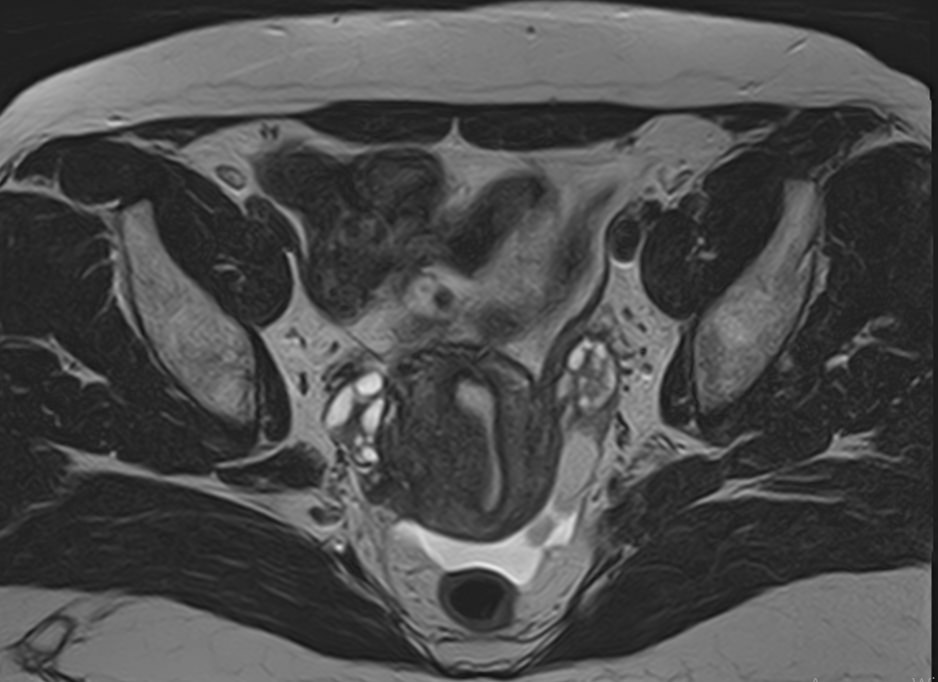

В клинике «Доступная медицина» МРТ яичников выполняется на современном томографе экспертного класса TOSHIBA VANTAGE TITAN 1,5 Тесла, который производит послойное сканирование анатомической области яичников в трех различных плоскостях с последующей цифровой обработкой полученных данных и построением трехмерных изображений исследуемой зоны.

Преимуществами МР сканирования является его высокая информативность, при этом безопасность, так как в основе метода лежит воздействие внешнего магнитного поля без использования рентгеновского излучения, что особенно важно при обследовании органов репродуктивной системы.

Стандартная МРТ яичников без контрастирования дает детальную информацию о состоянии яичников и окружающих тканей, но при необходимости уточнения патологических изменений, при проведении дифференциальной диагностики, внутривенно вводится контрастное вещество.

Что показывает МРТ яичников?

На МР-исследовании могут быть обнаружены:

• кисты;

• острое и хроническое воспаление, абсцессы;

• опухолевые процессы.